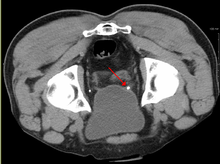

Imaging studies

Calcium-containing stones are relatively radiodense, and they can often be detected by a traditional radiograph of the abdomen that includes the kidneys, ureters, and bladder (KUB film).[28] Some 60% of all renal stones are radiopaque.[29][30] In general, calcium phosphate stones have the greatest density, followed by calcium oxalate and magnesium ammonium phosphate stones. Cystine calculi are only faintly radiodense, while uric acid stones are usually entirely radiolucent.[31]

Where available, a noncontrast helical CT scan with 5 millimeters (0.20 in) sections is the diagnostic modality of choice in the radiographic evaluation of suspected nephrolithiasis.[3][26][29][32][33] All stones are detectable on CT scans except very rare stones composed of certain drug residues in the urine,[28] such as from indinavir.

Ultrasound imaging of the kidneys can sometimes be useful, as it gives details about the presence of hydronephrosis, suggesting the stone is blocking the outflow of urine.[28] Radiolucent stones, which do not appear on KUB, may show up on ultrasound imaging studies. Other advantages of renal ultrasonography include its low cost and absence of radiation exposure. Ultrasound imaging is useful for detecting stones in situations where X-rays or CT scans are discouraged, such as in children or pregnant women.[34] Despite these advantages, renal ultrasonography is not currently considered a substitute for noncontrast helical CT scan in the initial diagnostic evaluation of urolithiasis.[32] The main reason for this is that compared with CT, renal ultrasonography more often fails to detect small stones (especially ureteral stones), as well as other serious disorders that could be causing the symptoms.[1]